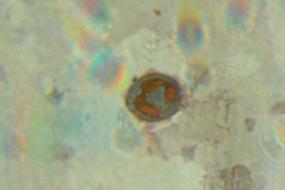

| Рисунок 3.3.2.1 Сегментоядерный нейтрофил с фагоцитированной микрочастицей латекса после 1 суток экспозиции при –40°С в хладоограждающем растворе №13

| Рисунок 3.3.3.2 Сегментоядерный нейтрофил с активными гранулами, содержащими катионные белки после 30 суток экспозиции при –40°С в хладоограждающем растворе №13